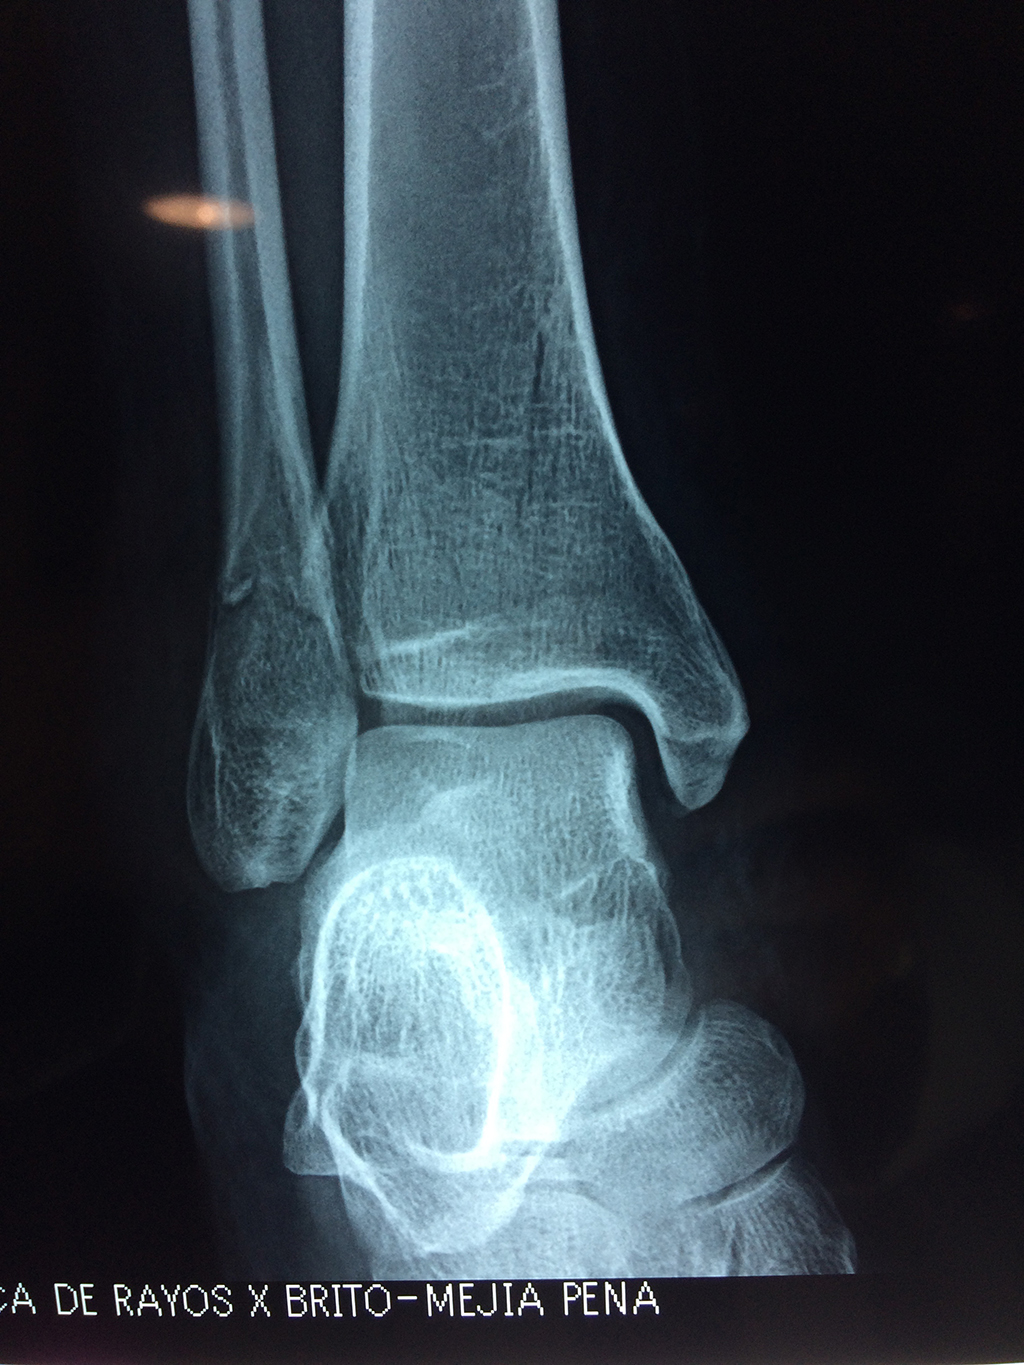

Cirugías de Peroné y Tibia

Una fractura de tobillo es la rotura de uno o más de los huesos del tobillo. Estas fracturas pueden ser:

Algunas fracturas de tobillo pueden requerir cirugía si:

Cuando se necesita cirugía, es probable que esta implique el uso de clavijas de metal, tornillos o placas para sostener los huesos en su lugar mientras la fractura se consolida. Los elementos de soporte pueden ser temporales o permanentes.